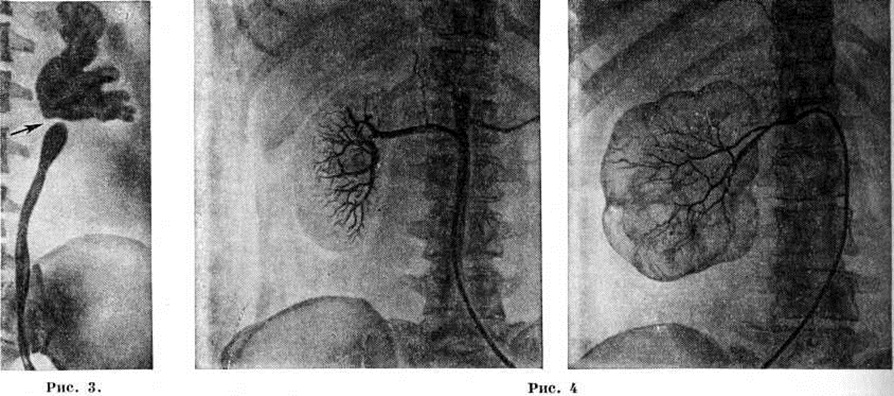

Травматический Гидронефроз развивается вследствие сдавления мочеточника гематомой в результате его повреждения (огнестрельное ранение, разрыв при операциях) с последующим образованием спаек или стриктуры. При всех видах механического затруднения оттока мочи в возникновении Гидронефроз имеют значение и функциональные нарушения лоханочно-мочеточникого сегмента. ПатогенезПри Гидронефроз процесс секреции и реабсорбции мочи сохраняется, но имеет место некоторое отставание эвакуации мочи из лоханки, что обусловливает накопление содержимого и повышение давления в ней. Это даёт право гидронефротическую почку почти всегда считать функционирующим органом, что доказано радиоизотопными исследованиями — из закупоренной почечной лоханки в ток крови реабсорбируются изотопы натрия, йода, коллоидного золота [Перски (L. Persky) с соавторами, 1955]. В начальных стадиях гидронефротической трансформации при стазе мочи в лоханке наступает гипертрофия мускулатуры лоханки и чашечек. Постепенно нарастающая гипертрофия спиральной мускулатуры чашечек приводит к резко повышенному давлению мочи на сосочек и форникальную зону. Это создаёт трудности нормальному выделению мочи из сосочков в почечную лоханку, в некоторой степени компенсируемые уменьшенной секрецией мочи. Однако это относительное равновесие функции почки продолжается недолго. Рабочая гипертрофия мышечных элементов чашечек и лоханки сменяется их истончением и разволокнением, что нарушает отток мочи и приводит к дилатации почечной лоханки и чашечек с последующей атрофией сосочков и почечной паренхимы. Одним из важных моментов в возникновении Гидронефроз является задержка выведения мочи из функционально деятельных участков почки, что наблюдается даже при кратковременных повышениях внутрилоханочного давления. Высокое давление в почечной лоханке вызывается не только поступающей в неё мочой, но и чрезмерным сокращением мускулатуры чашечек, особенно форникального и чашечного сфинктеров. А. Я. Пытель (1959) придаёт большое значение мышечной системе чашечек и лоханки в оттоке мочи по собирательным канальцам и межтканевой жидкости. Уже спустя 24 часа после закрытия просвета мочеточника начинается атрофия почечных пирамид вследствие сдавления их трансфорникальным отёком, сосочки постепенно уплощаются. Через 6—10 дней атрофия пирамид достигает большей степени, сосочки становятся вогнутыми. Наряду с деформацией форниксов происходит расширение просвета собирательных канальцев, облегчающее поступление мочи из лоханки в тубулярную систему. При полной окклюзии мочеточника происходят множественные форникальные разрывы, в результате чего создаётся рефлюкс мочи в почечное интерстициальное пространство, в кровеносную или лимфатические, систему. Повышенное внутри-паренхиматозное давление нарушает кровоток в сосудах мозгового вещества почки, что приводит к атрофии пирамид. Сдвиги кровообращения в кортикальных и медуллярных капиллярах сопровождаются изменениями кровообращения в паренхиме и тканевом обмене, а также кислородным голоданием, способствующими тотальной атрофии коркового вещества почки. Кьяудано (М. Chiaudano, 1958), Н. А. Лопаткин (1960) полагают, что гидронефротическая трансформация протекает по двум фазам: в первой атрофируется мозговое вещество, во второй — корковое. Наступающие изменения кровеносной системы почки, чашечек постепенно приводят к тотальному Гидронефроз Большая роль в патогенезе Гидронефроз принадлежит нарушениям эластической мембраны внутрипочечных сосудов, а также лимфатические, системе. Вследствие повышения проницаемости капилляров развивается отёк и компенсаторное расширение лимфатические, сосудов, участвующих в резорбции мочи, с последующим нарушением лимфообращения. В терминальной стадии гидронефротической трансформации после атрофии форниксов резорбция гломерулярного фильтрата происходит путём тубуловенозного рефлюкса. Таким образом, лоханочно-почечный рефлюкс (смотри) имеет безусловное значение при развитии Гидронефроз. Эти компенсаторные механизмы приводят к снижению давления мочи и способствуют сохранению почечной секреции на длительное время. Патологическая анатомия. Морфологически изменения при Гидронефроз зависят в первую очередь от стадии болезни. В начальных стадиях почка (независимо от внутри- или внепочечной локализации лоханки) мало отличается от здоровой. В основном патологический изменения выражены в чашечках и лоханке. Под действием повышенного внутрилоханочного давления увеличивается ёмкость чашечек и в значительной степени изменяется их конфигурация — они становятся круглыми, шейка их укорачивается и увеличивается в поперечном размере. Подобная картина чаще наблюдается при внутрипочечном расположении лоханки; она носит название гидрокаликоз (расширение одной или нескольких чашечек). Одновременно с увеличением размеров чашечек нарастает ёмкость лоханки; это происходит быстрее при внепочечном её расположении. Таким образом, к гидрокаликозу присоединяется и пиелоэктазия, а при низких локализациях препятствий развивается гидроуретеронефроз. Стенка лоханки постепенно истончается вследствие прогрессирующей атрофии гладких мышечных волокон и замены их соединительной тканью; погибают нервные окончания; облитерируются кровеносные и лимфатические, сосуды лоханки. Существует параллелизм между длительностью существования препятствия оттоку мочи и степенью нарушения нервно-мышечного тонуса лоханки. В терминальной стадии Гидронефроз лоханка представляет дряблый тонкостенный мешок, стенки которого в основном состоят из грубоволокнистой соединительной ткани. Прогрессивно растягивающаяся лоханка оттесняет почечную паренхиму к периферии, сдавливает форникальные вены и артериолы. В почечной паренхиме постепенно развиваются явления атрофии и склероза (рисунок 2), позже почка превращается в соединительнотканный мешок с отдельными остатками нормальной ткани. Наблюдаются и различные изменения сосудов почки — артерии становятся извитыми, удлинёнными, расширенными. Артериография удалённых почек и прижизненная серийная ангиография позволили обнаружить сужения магистральной почечной артерии, облитерацию и запустевание её ветвей. При этом, чем глубже выражена атрофия почки, тем уже их просвет, тем дальше отстоят ветви одна от другой (Н. A. Лoпаткин, 1961). В этой стадии Гидронефроз почка бывает резко увеличена в размерах, корковый слой её очень тонкий (цветной рисунок 1 и 2). Клиническая картинаВ течении гидронефроза принято выделять три стадии: I — начальную, II — раннюю, III — терминальную. Гидронефроз часто развивается бессимптомно и проявляется при вспышке инфекции, травме или случайно обнаруживается при пальпации брюшной полости. Симптомов, характерных только для Гидронефроз, нет. Наиболее часты боли в поясничной области разной интенсивности, постоянного ноющего характера, а в ранней стадии — в виде приступов почечной колики. Приступы сопровождаются тошнотой, рвотой и вздутием живота. Часто больные отмечают уменьшение количества мочи перед приступами и во время них и увеличение после разрешения приступа. В далеко зашедших стадиях Гидронефроз острые боли не характерны. Повышение температуры во время приступов боли может быть только при инфицированном Гидронефроз, что объясняется возникновением пиеловенозного рефлюкса. Важным симптомом при большом Гидронефроз является прощупываемое в подреберье опухолевидное образование. Гематурия (микро- и макроскопическая) — нередкий, иногда единственный симптом. В терминальной стадии заболевания функция почки резко нарушается. Явления почечной недостаточности появляются главным образом при двустороннем процессе. Осложнения — присоединение инфекции, образование вторичных камней и разрыв гидронефротического мешка при травме. ДиагнозПальпацией удаётся распознать Гидронефроз лишь в поздних стадиях. Хромоцистоскопия (смотри) является вспомогательным методом, позволяющим заподозрить Гидронефроз и судить о секреторной функции почечной паренхимы и о моторной функции лоханки и мочеточника. При Гидронефроз индигокармин на больной стороне выделяется с запозданием и вялой, слабо окрашенной струёй или вовсе не выделяется. Для более точного суждения о секреторной функции почки рекомендуется хромоцистоскопия с катетеризацией мочеточника, что даёт возможность судить о его проходимости и локализации в нем препятствия, о наличии и количестве остаточной мочи в лоханке; кроме того, представляет возможность получить мочу раздельно из каждой почки. Основная роль в диагностике Гидронефроз принадлежит рентгенологическое методам. Обзорная рентгенография позволяет определить размеры почки и иногда обнаружить камни. На экскреторной урограмме, произведённой через 10 минут после введения контрастного вещества в вену, выявляются слабо очерченные тени полостей почки вследствие большого разведения препарата остаточной мочой, содержавшейся в лоханке. Затем происходит накопление контрастного вещества (вследствие нарушения эвакуации мочи), и снимок (через 20 минут после первого) показывает изображение расширенных чашечек и лоханки. При значительных изменениях паренхимы накопление контрастного вещества замедляется и становится заметным на урограмме лишь через 1 — 2 часа после введения его в вену, а при резкой атрофии почки препарат не выделяется вовсе; в не которых случаях это может зависеть и от угнетения деятельности почки вследствие острой обтурации мочевых путей. Изображения на урограммах при Гидронефроз имеют разнообразную форму — от умеренной пиелоэктазии до большой круглой или овальной полости с резко расширенными чашечками; полости с чёткими ровными краями, что отличает Гидронефроз от пионефроза. На уретерограмме видны зоны стриктур, перегибов, атоничные мочеточники, а также обтекаемые контрастным веществом препятствия в нем, например, камни, опухоль. Поперечный перерыв тени в области лоханочно-мочеточникового сегмента характерен для клапана, добавочного сосуда (рисунок 3). Ретроградную пиелографию (смотри) при больших Гидронефроз в связи с опасностью тяжёлых осложнений целесообразно производить в день операции. После пиелографии в этих случаях необходимо извлекать катетер через 30—60 минут после опорожнения лоханки от мочи. В других случаях дренирование лоханки обеспечивает отток мочи и предотвращает возможность осложнений. Анализ мочи, раздельно взятой из почек, и бактериологических исследование её с определением чувствительности микрофлоры к антибиотикам при инфицированном Гидронефроз дополняют клинической, диагностику. Селективную артериографию (рисунок 4) для диагностики Гидронефроз производят сравнительно редко с целью уточнения стадии процесса изучения сосудистого рисунка почки, а также выявления добавочного сосуда (смотри Почечная ангиография). Изредка применяют чрескожную пункционную антеградную пиелографию (рисунок 5). Радиоизотопная ренография существенно дополняет рентгено л. исследование, особенно при двустороннем Гидронефроз, когда удаётся выявить сторону наибольшего поражения (смотри Ренография радиоизотопная). Дифференциальный диагноз проводят с различными заболеваниями почек и органов брюшной полости. При Гидронефроз, протекающем с болевым синдромом, следует дифференцировать Гидронефроз с нефролитиазом (смотри Мочекаменная болезнь), нефроптозом (смотри). Обзорная рентгенография или пневмопиелография подтверждает или исключает нефролитиаз. При нефроптозе боли возникают главным образом при движениях и физических напряжениях и быстро стихают в горизонтальном положении. Если при пальпации обнаружена опухоль, необходимо решить, расположена ли она в забрюшинном пространстве или в брюшной полости. Это достигается урографией (смотри) и введением газа в забрюшинное пространство (смотри Пневморетроперитонеум). В отличие от Гидронефроз, опухоль почки малоподвижна, плотна, бугриста. На пиелограмме характерны деформация лоханки или «ампутация» чашечек (дефекты наполнения). При поликистозе обе почки увеличены, бугристы; отмечаются явления почечной недостаточности; типична и пиелограмма — удлинённая лоханка и вытянутые в виде полулуний чашечки. Солитарной кисте почки свойственно сдавление полостей чашечек и лоханки, видимое на пиелограмме. Лечение должно быть направлено на устранение причины, вызвавшей развитие Гидронефроз, и сохранение почки. Среди различных методов хирургического лечения наиболее распространены пластические.